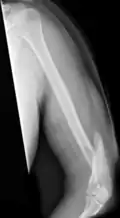

Humerus fracture

| Midshaft humerus fracture with callus formation | |

A humerus fracture is a break of the humerus bone in the upper arm.[1] Symptoms may include pain, swelling, and bruising.[1] There may be a decreased ability to move the arm and the person may present holding their elbow.[2] Complications may include injury to an artery or nerve, and compartment syndrome.[2]

The cause of a humerus fracture is usually physical trauma such as a fall.[1] Other causes include conditions such as cancer in the bone.[2] Types include proximal humeral fractures, humeral shaft fractures, and distal humeral fractures.[1][2] Diagnosis is generally confirmed by X-rays.[2] A CT scan may be done in proximal fractures to gather further details.[2]

Treatment options may include a sling, splint, brace, or surgery.[1] In proximal fractures that remain well aligned, a sling is often sufficient.[2] Many humerus shaft fractures may be treated with a brace rather than surgery.[2] Surgical options may include open reduction and internal fixation, closed reduction and percutaneous pinning, and intramedullary nailing.[2] Joint replacement may be another option.[2] Proximal and shaft fractures generally have a good outcome while outcomes with distal fractures can be less good.[2] They represent about 4% of fractures.[2]